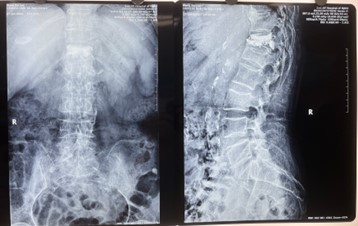

C形臂X光機作為手術中的重點設備,能準確定位,手術過程中即時觀看、即時做決策,在C形臂X光機的指導下,醫生能迅速、精準確定患者手術的部位。從而極大縮短手術時間,提高手術效率和質量,減輕患者痛苦,讓手術更加快捷且安全。

對比一些9英寸的平板C形臂,普愛醫療PLX119C大平板C形臂,30CM*30CM想(30CM*30CM)的成像范圍,一次性可成像5節腰椎,有效減少小視野C形臂難以一次性確定傷椎,可能需要進行多次拍攝的問題,使得手術效率更快、更準確。